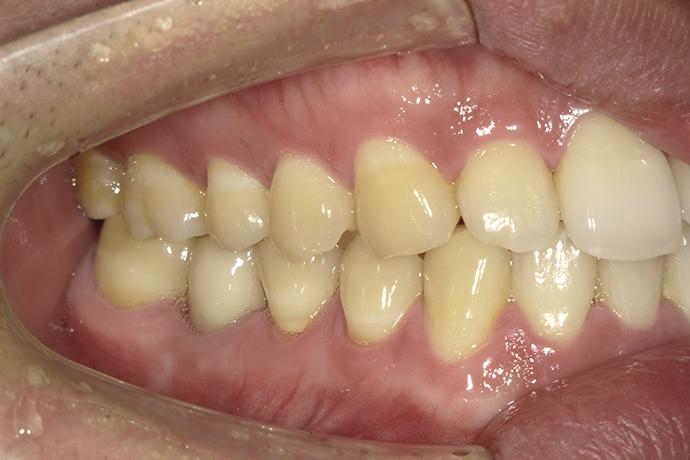

術前-缺牙及殘根

術前-

缺牙及殘根